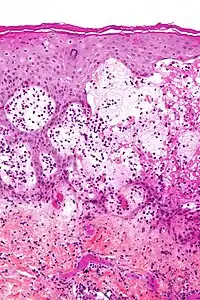

| Micrograph of gestational pemphigoid showing the characteristic subepidermal blisters and abundant eosinophils. HPS stain. | |